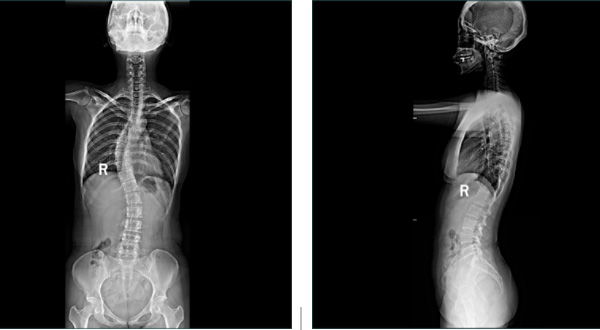

近日,玉溪市中醫(yī)醫(yī)院放射科島津C200第五代動(dòng)態(tài)大平板透視攝影系統(tǒng)投入使用,該設(shè)備可開展全脊柱、雙下肢全長檢查。高清攝影、快速診斷、及時(shí)治療,實(shí)現(xiàn)了全脊柱、雙下肢全長檢查的“無縫拼接”,是脊柱側(cè)彎和下肢畸形等骨科疾病術(shù)前術(shù)后X線檢查的首選方法。

放射科主任吉德磊介紹:“以前拍片子需要好長時(shí)間,需多次擺位。由于平板探測(cè)器最大規(guī)格一般只有43cm左右,而脊柱和下肢全長一般超過了這個(gè)長度,現(xiàn)采用新系統(tǒng)實(shí)現(xiàn)全脊柱及雙下肢全長X線攝片,能直觀的顯示全脊柱、雙下肢全長的整體形態(tài),在一張照片上可獲得較清晰、完整的全景圖像顯示,并可進(jìn)行相關(guān)長度測(cè)量、角度測(cè)量等應(yīng)用。”

成功解決了在觀察頸椎至尾椎的脊柱側(cè)彎或其他病變時(shí)不能一次成像的問題。

常規(guī)DR不能一次性完成全脊柱或全下肢X光影像拍攝,需分別拍攝頸椎、胸椎、腰椎、骶尾椎的X光片,只能觀察到局部的側(cè)彎情況,看不到三者之間的連續(xù)性,增加了這類疾病的診治難度。

市中醫(yī)醫(yī)院放射科這臺(tái)高端懸吊DR具有千萬級(jí)像素,利用其特有的“無縫拼接”技術(shù),可獲得一幅完整的全脊柱和全下肢影像,為臨床在脊柱側(cè)彎畸形和下肢骨關(guān)節(jié)病變?cè)\斷、治療方案制定及術(shù)后復(fù)查提供精準(zhǔn)的測(cè)量。

2、對(duì)于脊柱側(cè)彎的診斷治療、手術(shù)方案的制定等都有著極其重要的參考價(jià)值。